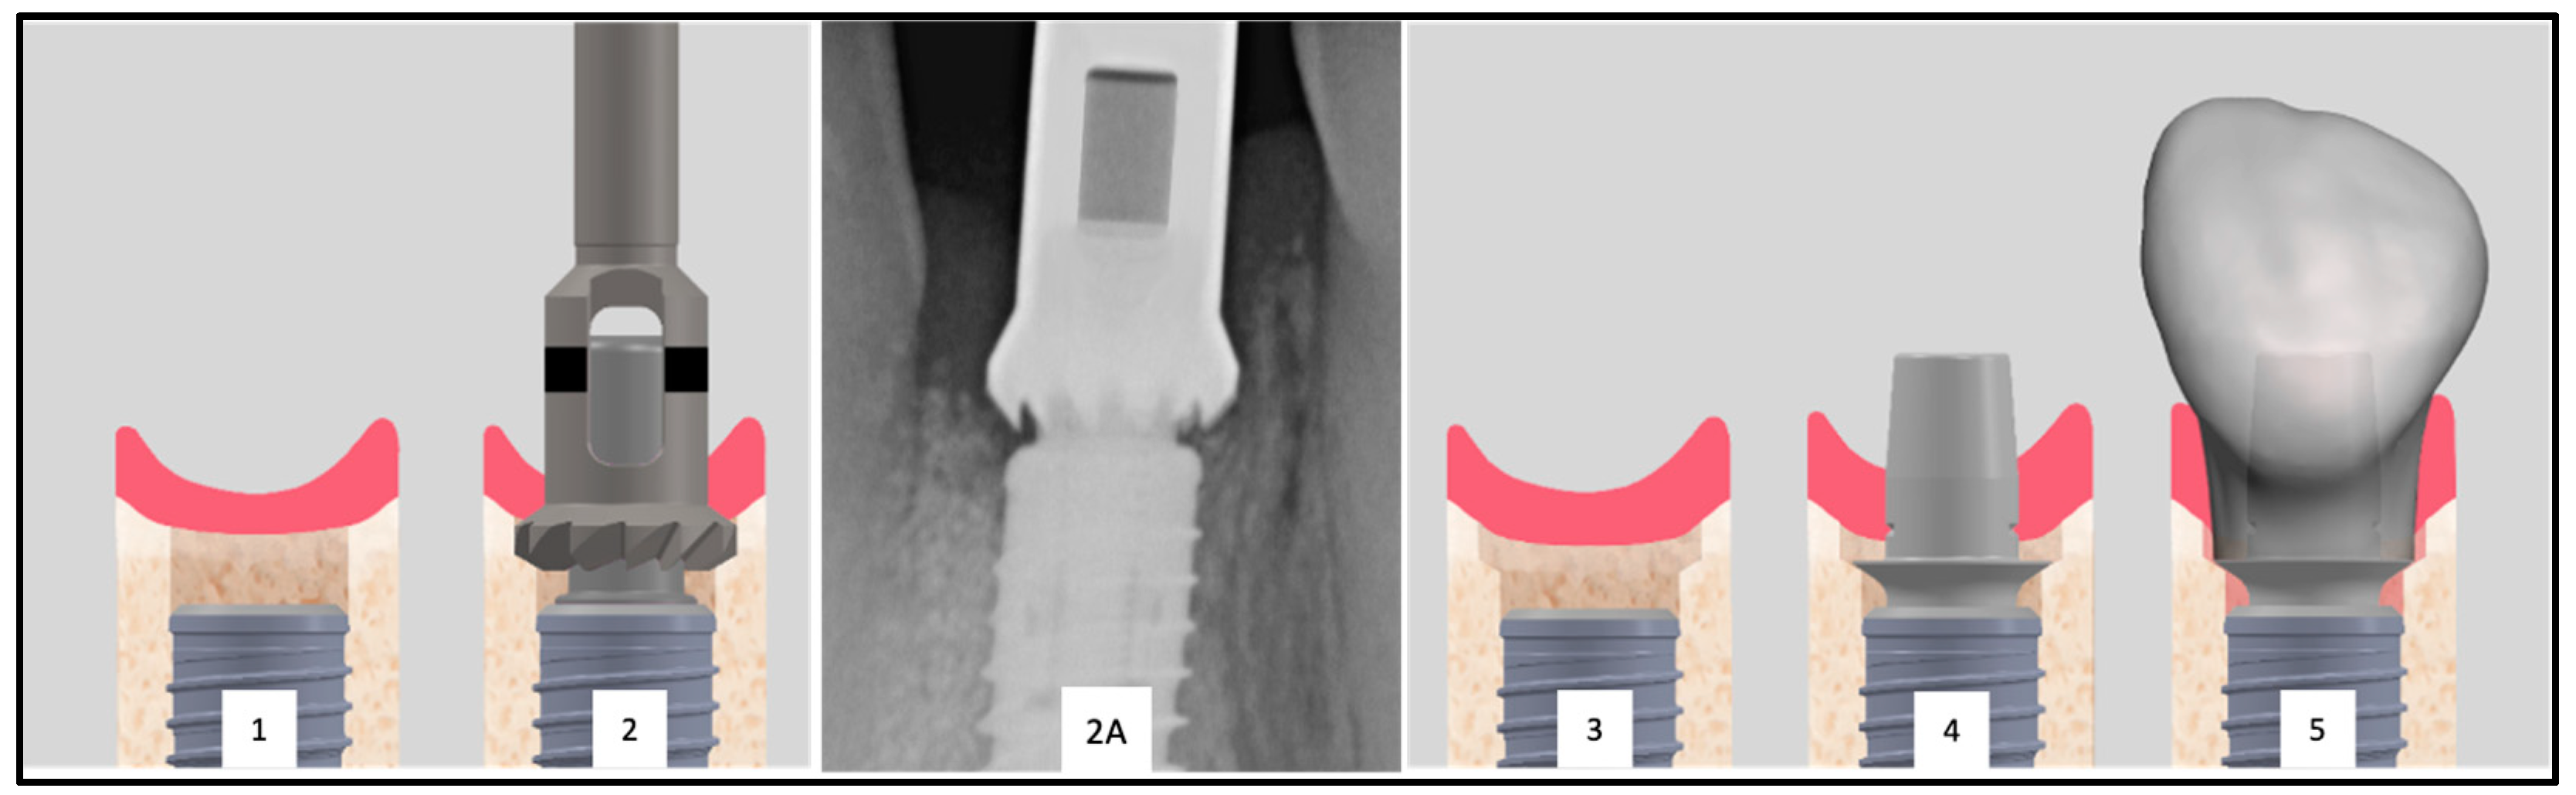

Furthermore, the subcrestal placement of the implant (1.5 mm) led to proximal bone overhangs, requiring adjustment of the supracrestal complex with a bone profiler matching the implant and abutment size. This also enabled the optimized shaping of the emergence profile after implant insertion by contouring the crestal bone with the Bone Profiler System (SIC Invent©, Basel, Switzerland) (Figure 2). This system is specifically designed to shape the bone above the implant shoulder to match the desired emergence profile, with the profiler’s milling angle corresponding to that of the abutment (30°). The Bone Profiler shown in Figure 1 is a bone trephine drill used with a surgical contra-angle handpiece operating at approximately 50 rpm. It includes a mounted guide pin for precise control. The system consists of trephine drills in various diameters (4.0, 4.5, 5.0, and 6.0 mm), corresponding to the implant and abutment diameters, allowing for the shaping of the planned ideal emergence profile in the crestal bone. To prevent damage to the implant shoulder, the guide pin is securely fixed to the implant, directing the Bone Profiler and limiting its depth to 0.02 mm above the implant shoulder.

The Bone Profiler with a circular diameter of 4.5 mm was used for the titanium bases with a diameter of 4.05 mm at the crown-abutment junction (CAJ), and the profiler with a preparation diameter of 5 mm was used for titanium bases with a CAJ diameter of 4.5 mm. This ensured a lateral clearance of 0.2–0.25 mm for the base of the emerging crown (Figure 2).

Figure 2. Inserted implant with clearly visible proximal bone overhangs (1). To allow the placement of the provisional restoration a bone profiler is used (2). Radiographic image of an exemplary Bone Profiler (2A). This tool reduces the bone of the supracrestal complex according to the diameter of the abutment (2). The conditioned bone is visible (3). The conditioning of the bone enables the seamless placement of the abutment (4) and the restoration (5).